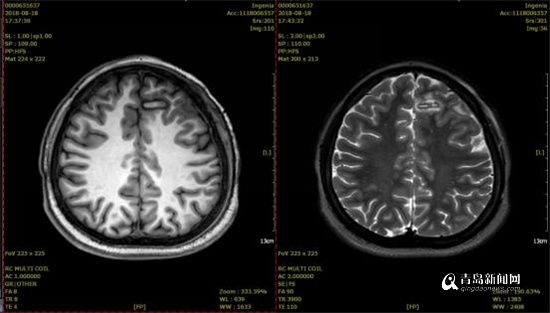

SEEG引导下的射频热凝(RF-TC)术后复查,显示毁损范围满意。

术后的脑电图监测结果显示,正是术前高度怀疑的额叶内侧面前扣带回为癫痫起源,同时予以患者小电流刺激相应的电极触点即可诱发患者平时的惯常发作,进一步证实了之前判断。SEEG术后第5天,患者在完全清醒状态在接受了SEEG引导下射频热凝毁损术,术中毁损了患者的癫痫病灶,毁损过程中患者没有一丝疼痛等不适,术后没有任何神经功能障碍,且术后效果立竿见影,当天停用其中一种抗癫痫药物后也没有再次癫痫发作,拔出颅内深部电极后复查颅脑MRI见毁损范围与之前判断的癫痫病灶重叠良好,患者满意出院。